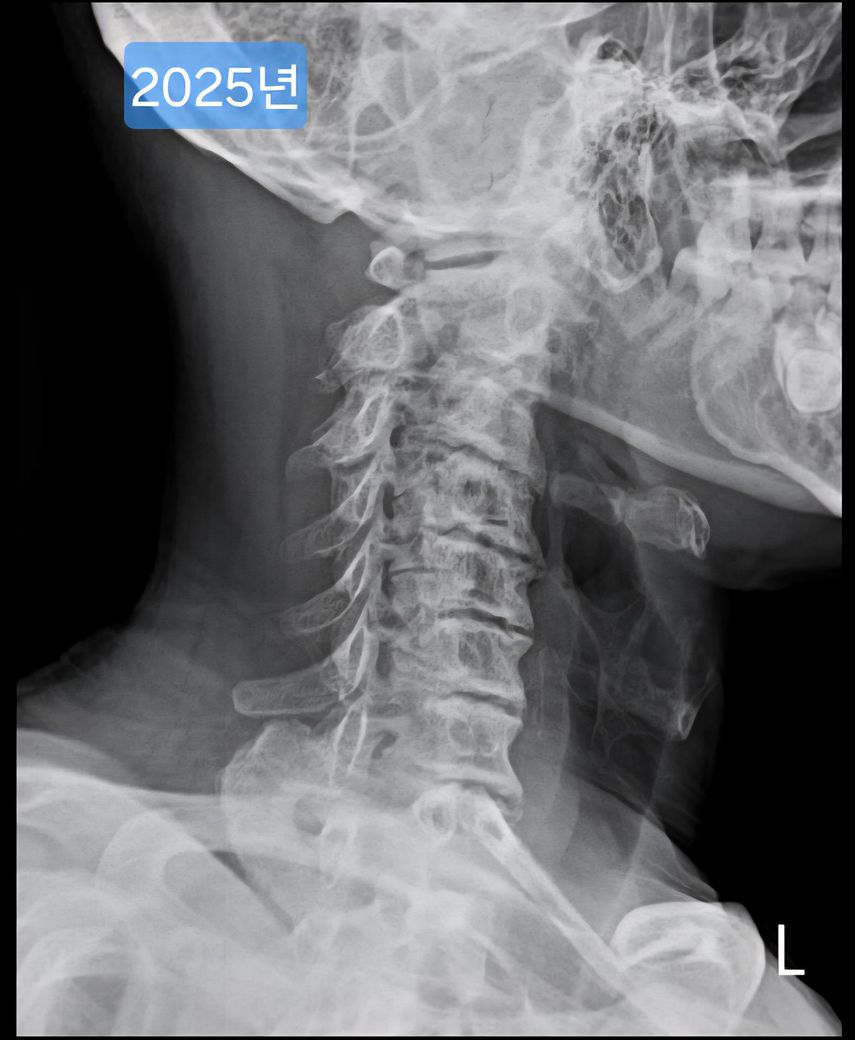

목 엑스레이 사진입니다. 많이 심각한걸까요?

며칠전 운동하다가 어깨에서 뚝 소리가 나고 그 이후에 큰 통증은 없는데 어깨 움직일때 뚝 하는 소리가 계속 나서

정형외과에 갔습니다.

어깨 엑스레이를 찍었는데 어깨는 엑스레이상 큰 문제는 발견되지 않았고..

선생님이 같이 찍힌 목사진을 보시더니 심각하다며..

경추사이 간격도 좁고, 일자목이고.. 목으로만 보면 추정 나이가 80세정도 된다고 하셨습니다..(전 50초반입니다.)

목이 정상이다가 갑자기 이렇게 진행된 경우면 위험하고..

원래 이런 형태로 오랫동안 유지된 사람이라면 뭐 그렇게 심각한건 아니니 이렇게 살아야한다고 말씀하시더라구요.

오늘 찍은 2025년도 엑스레이와 9년전 사진을 업로드 해 드리겠습니다.

(이미지에 좌측상단에 해당연도 표시했습니다.)

1. 2016년과 2025년도 목이 상태가 많이 변했나요?

제가 보기엔 9년전에도 경추사이 간격이나 일자목이나 비슷한듯 보여서요.

->우선 사진상으로 봤을 땐 과거에도 충분히 경추 사이의 간격이 좁고, 목의 커브는 C자의 만곡 보단 일자목과 비슷해보이며 시간이 지나면서 누구나 겪는 퇴행성의 과정으로 보여집니다.

다만 가장 정확한것은 해당 병원에 다시 내원하셔서 과거 사진을 첨부하여 한번 더 판독 소견을 들어보시길 바랍니다.

9년 전과 비교했을 때 경추 간격과 일자목 형태가 크게 달라진 것 같지 않아 상태가 오래 유지 된 것으로 보입니다. 오랫동안 비슷한 형태라면 큰 통증이나 신경 증상이 없다면 생활에 지장을 주지 않는 범위일 수 있습니다.

진료보신 선생님이 말씀하신 것 처럼 엑스레이 사진은 많이 안좋습니다. 단순 엑스레이만으로는 알 수 있는 부분들이 적기 때문에 통증이 지속된다면 MRI 촬영 등 추가 검사 필요하겠으며, 말씀하신 것 처럼 낮은 베개 사용하는게 좋습니다.